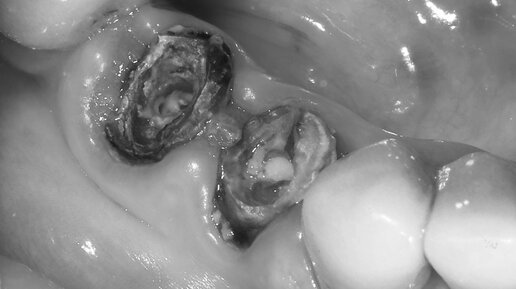

НЕ НА ЧТО СТАВИТЬ КОРОНКИ?

На зуб, разрушенный ниже уровня десны, нельзя поставить коронку?

Можно🤓 ⚙️Ортопедия, пародонтология — Алексей Фролов @dr.alexey.frolov НЕОБХОДИМА КОНСУЛЬТАЦИЯ СПЕЦИАЛИСТА🤓